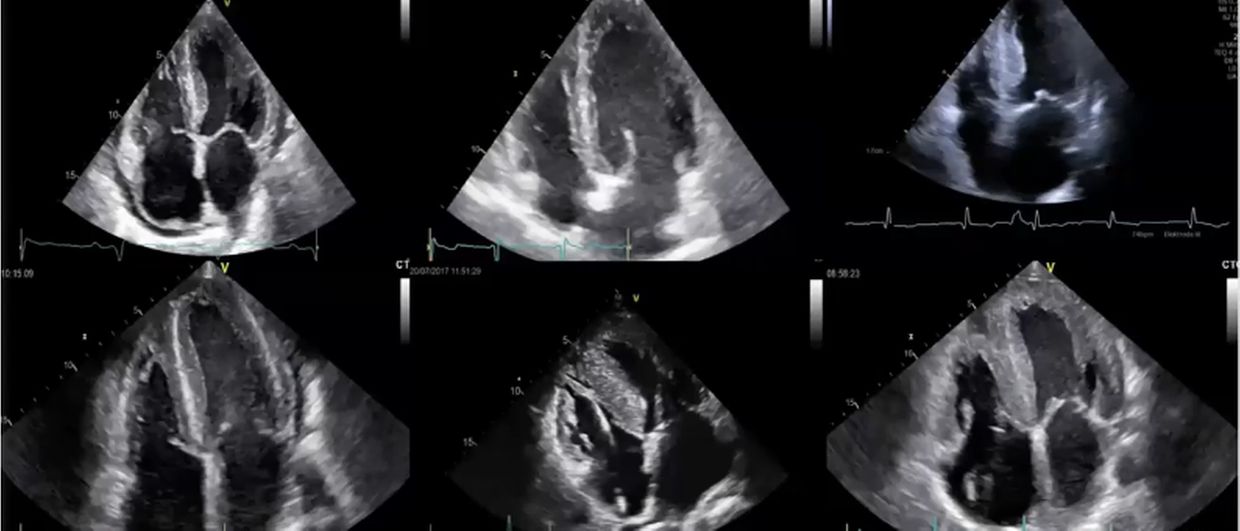

Der Stellenwert der Echokardiografie als Screening-Tool und zur Verlaufskontrolle bei hypertrophen Kardiomyopathien steht im Fokus dieses Videolearnings. Sie erfahren, warum mit der Echokardiografie keine endgültige Diagnose möglich ist, diese aber gegebenenfalls die weitere Abklärung anstößt.